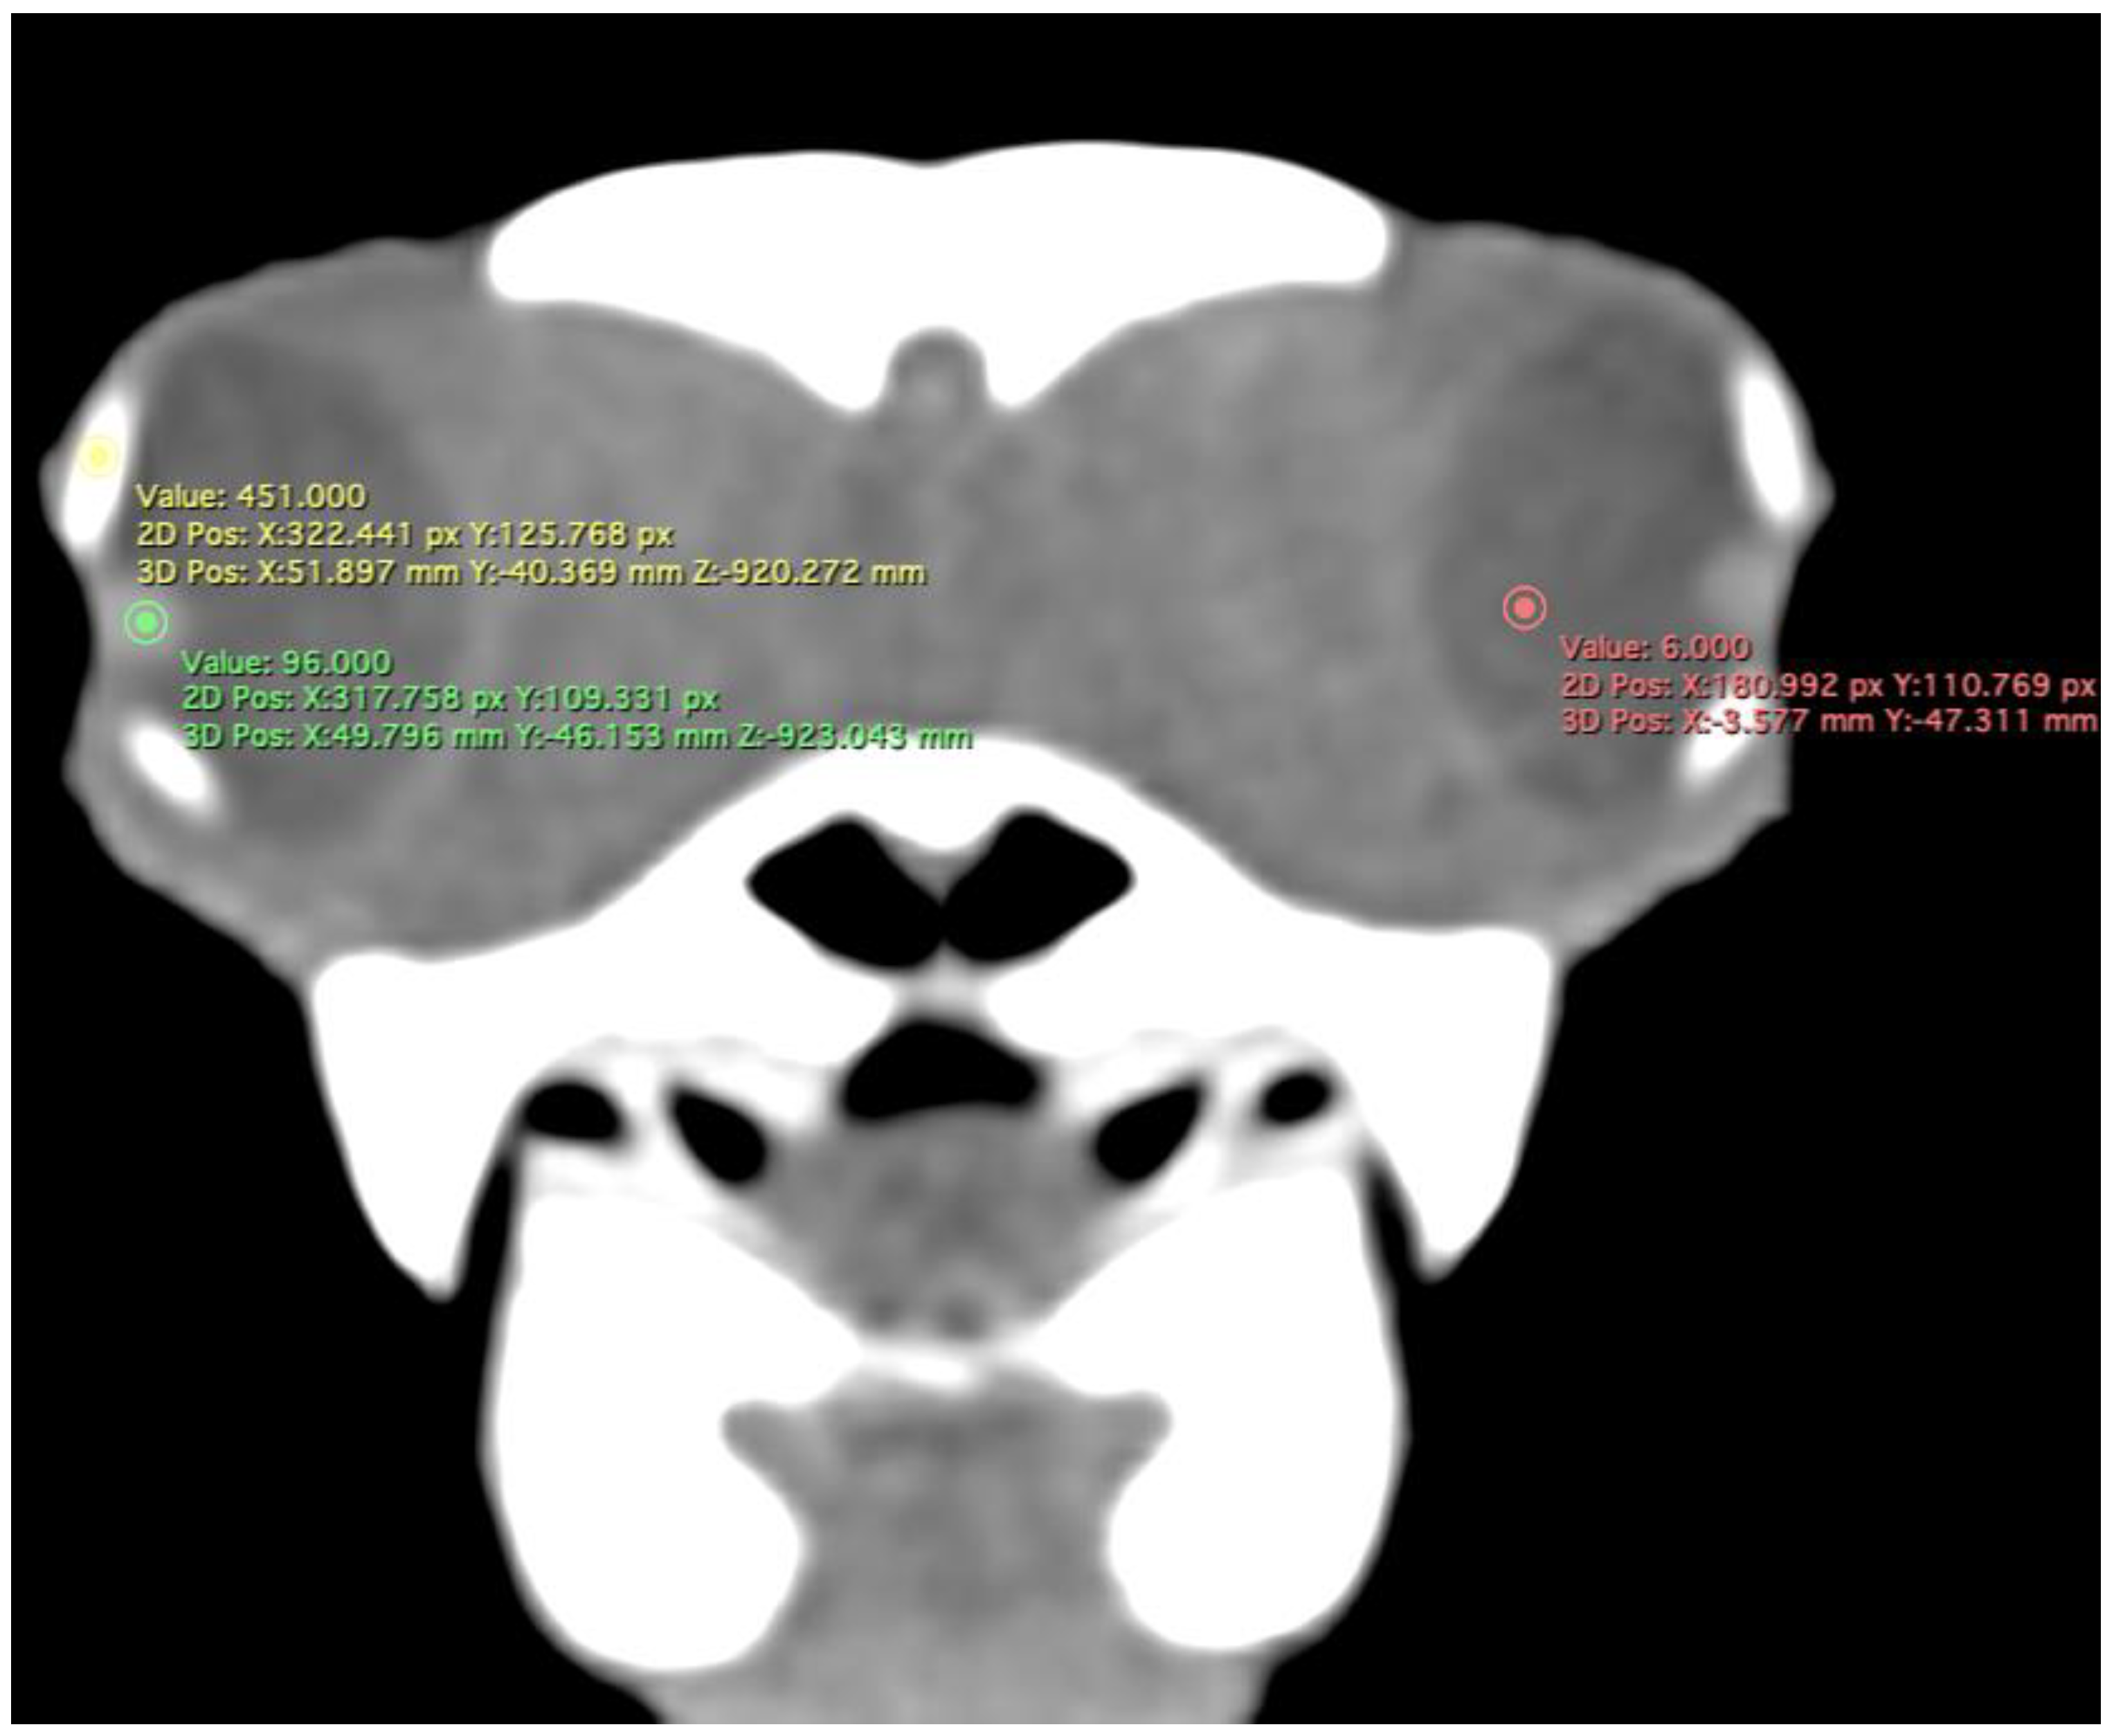

- Attenuation of the sclerotic ring and lens, taken in the dorsal area and vitreous humour expressed in Hounsfield Units (HU) (Figure 4).

Figure 4. Transverse CT image in soft tissue window of the C. caretta head. Regions of interest (ROI) indicating the areas used to measure mean attenuation in Hounsfield Units (HU) of the lens (green circle), sclerotic ring (yellow circle), and vitreous humour (red circle).

Concerning attenuation, the three circles (yellow, green, and red) indicate the areas used to describe the mean attenuation of different structures of the eyeball. Therefore, the sclerotic ring (yellow circle) was hyperattenuated (mean 353.85 HU: range = 203–500), and the lens (green circle) showed median attenuation (mean 98.85 HU; range = 81–116). Nonetheless, the vitreous chamber (red circle) was hyperattenuated (mean 17.80 HU; range = 7–28) with the adjacent structures (Figure 4).